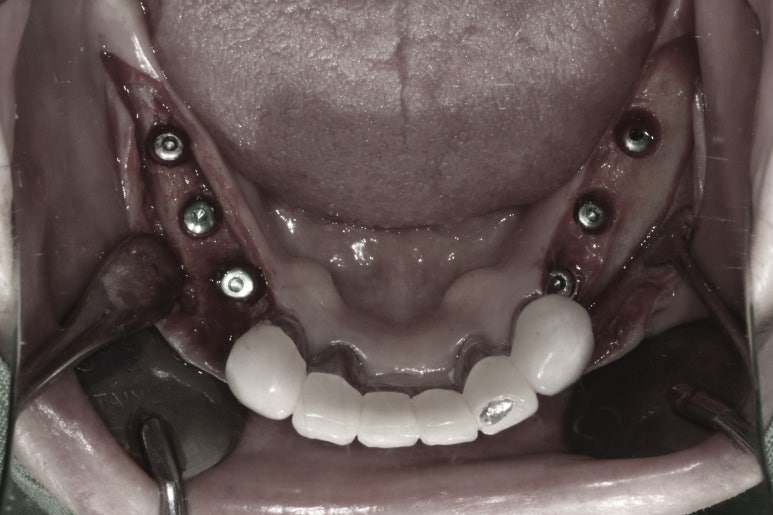

임플란트 2차 수술

아래턱뼈에 식립한 임플란트의 경우, 약 2달 정도의 치유기간만 주어지면 충분한 골유착을 기대할 수 있습니다.

임플란트를 잇몸 안에 모두 묻어놓았기 때문에 (submerged) 추후에 임프란트 보철물을 연결할 수 있도록 치유지대주 (healing abutment)를 연결해주어야 합니다.

이 간단한 시술을 임플란트 2차 수술이라고 부릅니다.

임플란트 2차 수술을 얘기하면, 대부분의 환자분들이 또 수술을 해야하냐고 싫어하시지만... 임플란트 2차 수술은 학술적으로 보았을 때, 단순히 뚜껑을 하나 바꿔껴내는 행위는 아닙니다.

추후 제작될 임플란트 보철물 주변의 잇몸의 성상을 조성할 수 있고, 경우에 따라 잇몸이식술도 시행하여 보다 관리가 용이한 환경을 만들어내는 소수술이라고 보시는게 맞습니다.

아래턱 어금니 임플란트에 임플란트 2차 수술을 시행하고나서 약 10일 뒤 실밥을 제거합니다.

이제 임플란트 인상채득을 시행합니다.

임플란트 보철물 제작을 위한 구강 스캔

각 임플란트에 연결된 치유지대주를 제거하고, 스캔 바디를 연결한 뒤 구강스캐너를 사용하여 인상채득 (뽄뜨기)을 시행합니다.